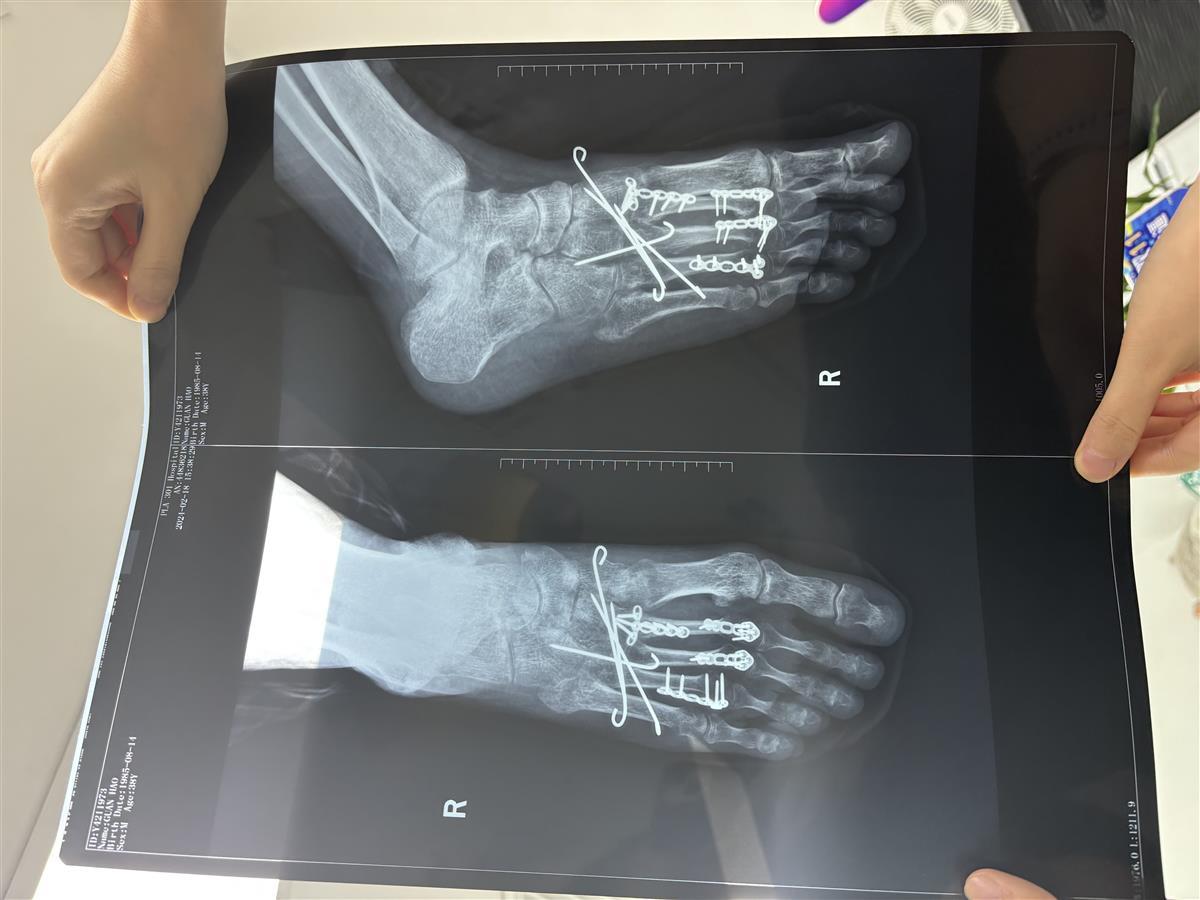

关先生当晚被送往罗湖区人民医院治疗,后转到北京的医院。根据医院诊断,关先生“右足第2、3、4跖骨骨折”,关先生的右脚被植入4块钢板和4根钢钉。经过近10个月的恢复,关先生走路还需要依靠拐杖。

关先生脚部骨折